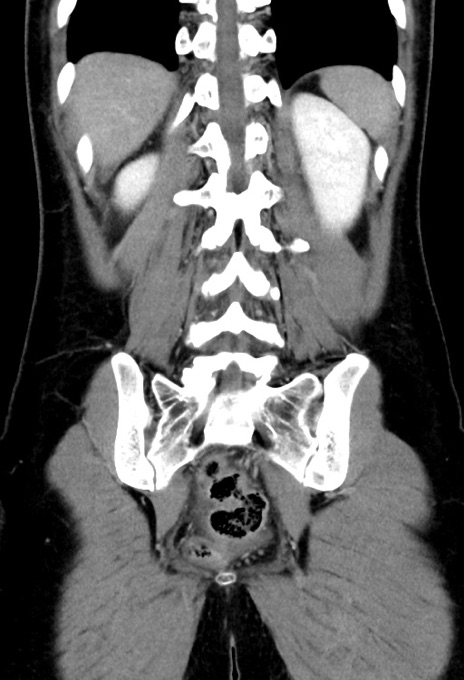

症例17(冠状断像)

【症例】20歳代女性

【主訴】嘔吐、下腹部痛

【現病歴】昨日夕食後に嘔吐し下腹部痛が出現。本日になっても嘔吐持続し改善しないため来院。

【身体所見】意識清明、BT 37.2℃、BP 108/67mmHg、腹部:平坦、やや硬、下腹部正中から右にかけて圧痛あり、反跳痛軽度あり、tapping pain(+)。

【データ】WBC 13600、CRP 14.94